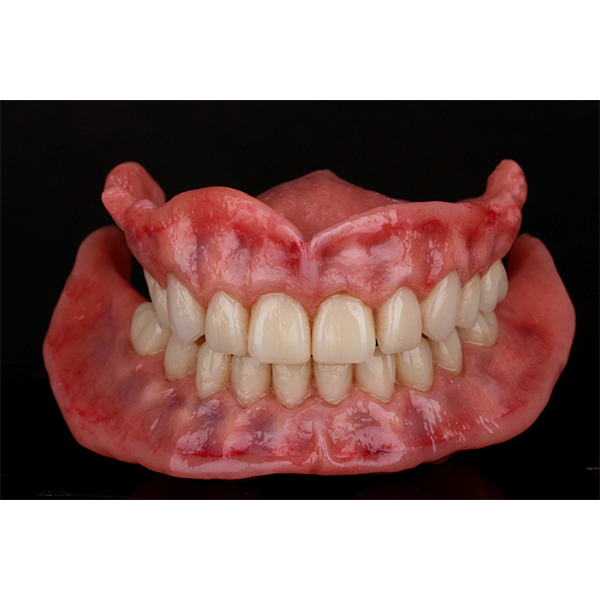

Après la mise en moufle et l'ébouillantage, les dents ont été repositionnées, conditionnées et des caractérisations blanchâtres, pourpres, orange clair, bleues et roses ont d'abord été réalisées au niveau du le bouclier labial. La base a ensuite été incrustée de résines pour prothèses de couleurs orange-rouge, rouge foncé, rouge clair, rose et rose foncé, et tous les polymères à chaud ont été pressés en une seule fois. Après le stockage sous pression, les prothèses finies ont été démouflées, finies et polies. La stratification anatomique tridimensionnelle de VITAPAN EXCELL en masse d'émail, de collet et de dentine avait un aspect absolument naturel dans l'anatomie muco-gingivale reproduite de la base prothétique. Le patient a pu s'habituer rapidement à sa nouvelle prothèse, notamment grâce à l'effet esthétique réussi. Après une courte phase d'adaptation et des corrections minimes dans l'environnement biodynamique, il s'est très bien débrouillé avec sa première restauration prothétique amovible complète et en était pleinement satisfait.